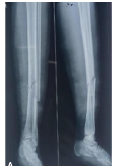

Representative case

A 45-year-old male sustained an AO type 23-B3 distal radius fracture following a road traffic accident. CT imaging with 3D reconstruction confirmed the fracture configuration. The fracture was approached dorsally and stabilized using dorsal and radial column plates, with additional K-wire support for the dorsal column. At 12-month follow-up, radiographs demonstrated maintained alignment, and functional assessment revealed satisfactory recovery (Fig. 5 and 6).